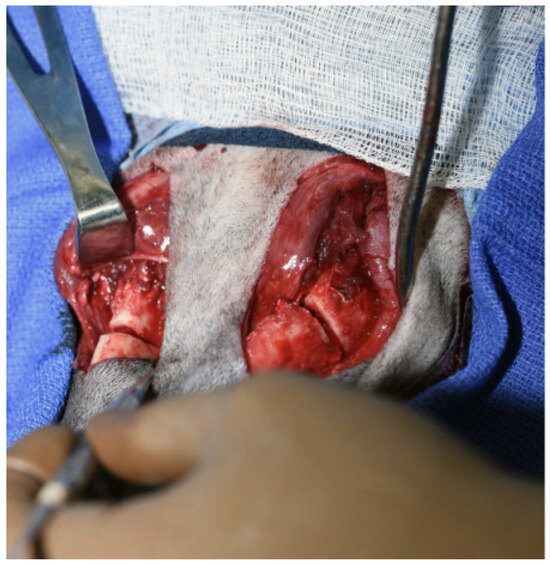

Figure 4.

A surgical incision was made on either side of the mandibles and a bilateral mandibular wedge ostectomy was performed using an oscillating bone saw 2 cm rostral to the border of the ventral ramus.

The patient was placed in dorsal recumbency and aseptically prepped from the level of the second tracheal ring to the rostral mandible and laterally to the ventral border of the zygomatic arch. An incision was made bilaterally over the caudal two-thirds of the ventral border of the mandibles and through the platysma muscle for exposure of the periosteum. The myloglossus and digastricus muscles were elevated from their attachments on the bone. A bilateral mandibular wedge ostectomy was performed, and bone plates and screws were used on either side to stabilize the mandibles to allow the mouth to remain permanently open to allow drinking, eating, and panting. (Figure 4 and Figure 5). The proposed ostectomy was outlined on the lateral and medial surfaces of each mandible. An oscillating bone saw was used to perform osteotomies along the medial and lateral aspects of each mandible, avoiding the mandibular canal. An osteotome was used to separate any remaining attachments between bones. The oral opening was visualized by a nonsterile assistant, and a spacer was placed to maintain an opening of approximately 3.5 cm. Bone was removed with the sagittal saw to create a closing wedge ostectomy to maintain the desired oral opening and maintain cortical contact of the mandible. Six-hole, 3.5 mm dynamic compression plates were placed on the ventrolateral aspect of the right and left mandibles with self-tapping, cortical screws to oppose the ostectomy sites, taking care to avoid tooth roots. Cancellous bone from the removed bone wedges was placed at the ostectomy lines. A minor operative complication was left mandibular artery trauma with hemorrhage that was controlled with bone wax. The post-operative radiographs confirmed both reduction and stabilization of the mandibular ramus bilaterally by means of the two plates. The tooth roots were avoided with screw placement (Figure 5 and Figure 6). The 3.5 cm opening was maintained between the upper and lower incisors postoperatively (Figure 7).